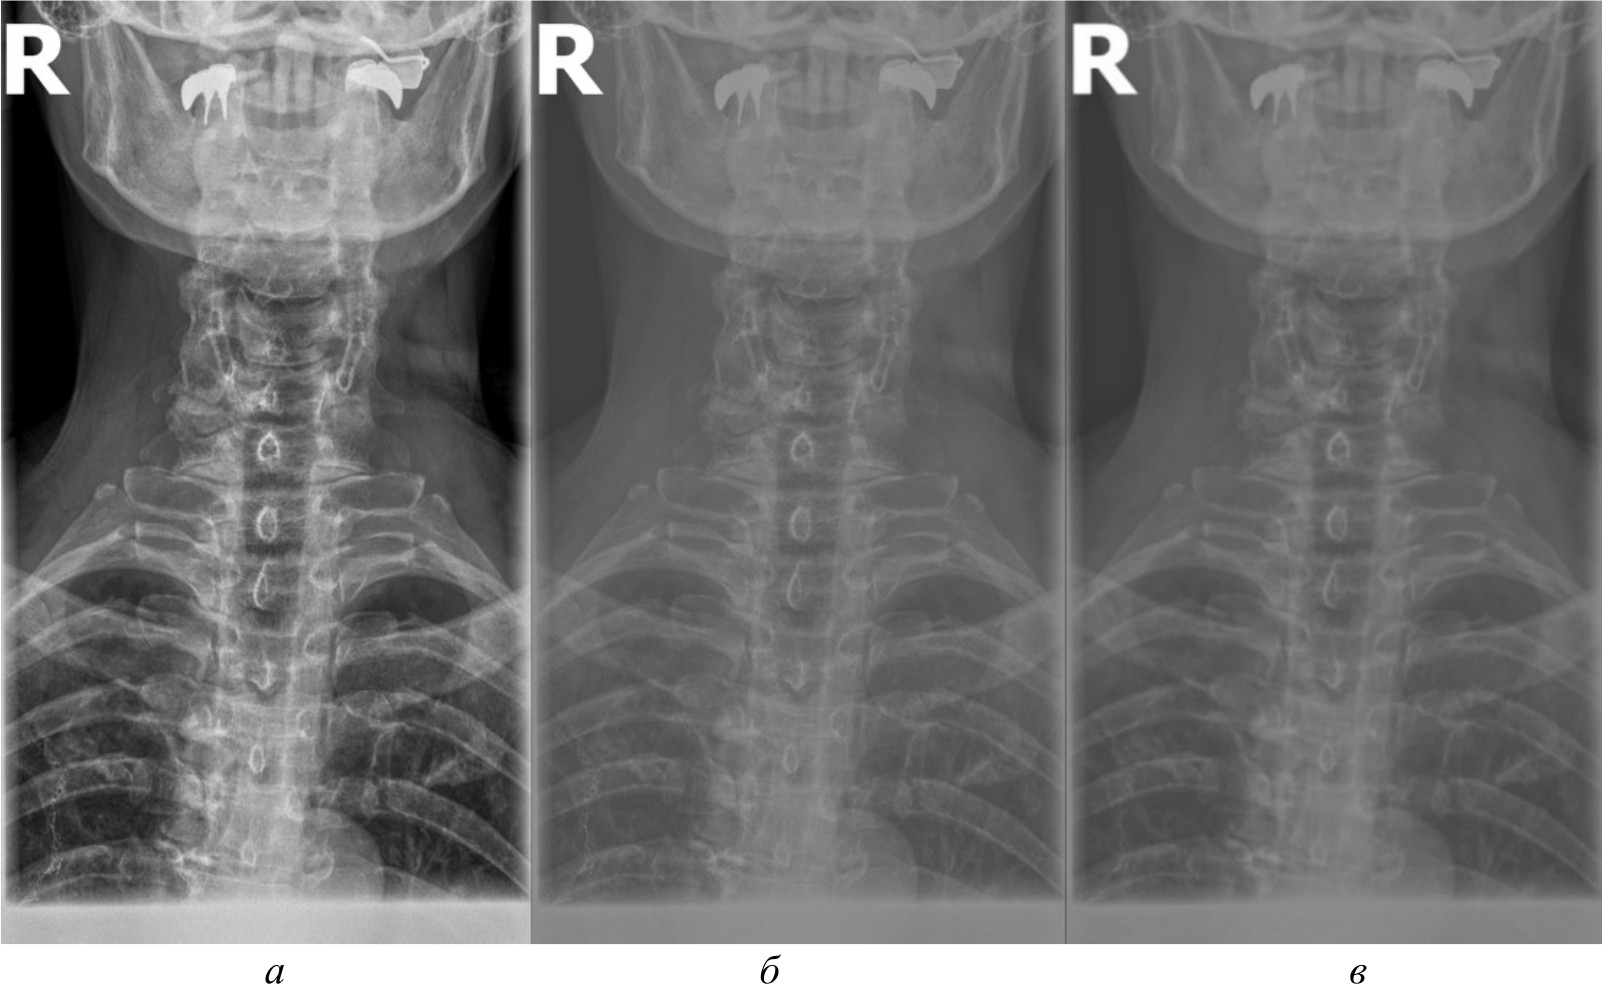

На рис. 4, 5 и 6 представлены результаты работы детектора Харриса, алгоритма Shi-Tomasi и SIFT при различных методах предварительной обработки изображений.

Рис. 4. Результаты работы детектора Harris на изображении, полученном при помощи специализированного программного обеспечения (а); результаты работы детектора Harris при методе адаптивной эквализации гистограммы (б); результаты работы детектора Harris при методе стандартной эквализации гистограммы (в); результаты работы детектора Harris при методе гамма-коррекции (г)

Рис. 5. Результаты работы алгоритма Shi-Tomasi на изображении, полученном при помощи специализированного программного обеспечения (а); результаты работы алгоритма Shi-Tomasi при методе базового отображения в Python (б); результаты работы алгоритма Shi-Tomasi при методе базового отображения Python с применением медианного фильтра (в); результаты работы алгоритма Shi-Tomasi при методе адаптивной эквализации гистограммы (г); результаты работы алгоритма Shi-Tomasi при методе стандартной эквализации гистограммы (д); результаты работы алгоритма Shi-Tomasi при методе гамма-коррекции (е)

Рис. 6. Результаты работы алгоритма SIFT на изображении, полученном при помощи специализированного программного обеспечения (а); результаты работы алгоритма SIFT при методе адаптивной эквализации гистограммы (б); результаты работы алгоритма SIFT при методе стандартной эквализации гистограммы (в)